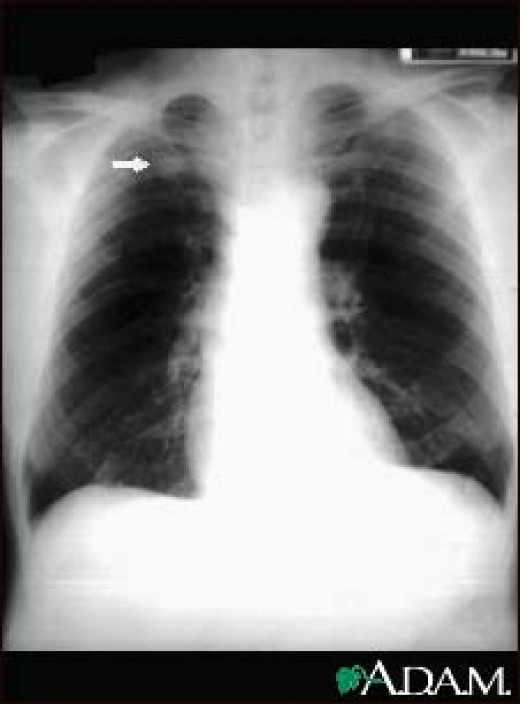

Chest x ray Tuberculosis healed, (TB), Inactive TB YouTube Sample X Ray Result With Tuberculosis there are two types of tests for tuberculosis (tb) infection: What to expect, results, and more. a sample of blood is sent to a lab. One lab test finds out whether certain immune system cells can recognize. A positive test result for tb infection. Getty images (2) the likelihood that an. a positive test result for tuberculosis. Sample X Ray Result With Tuberculosis.